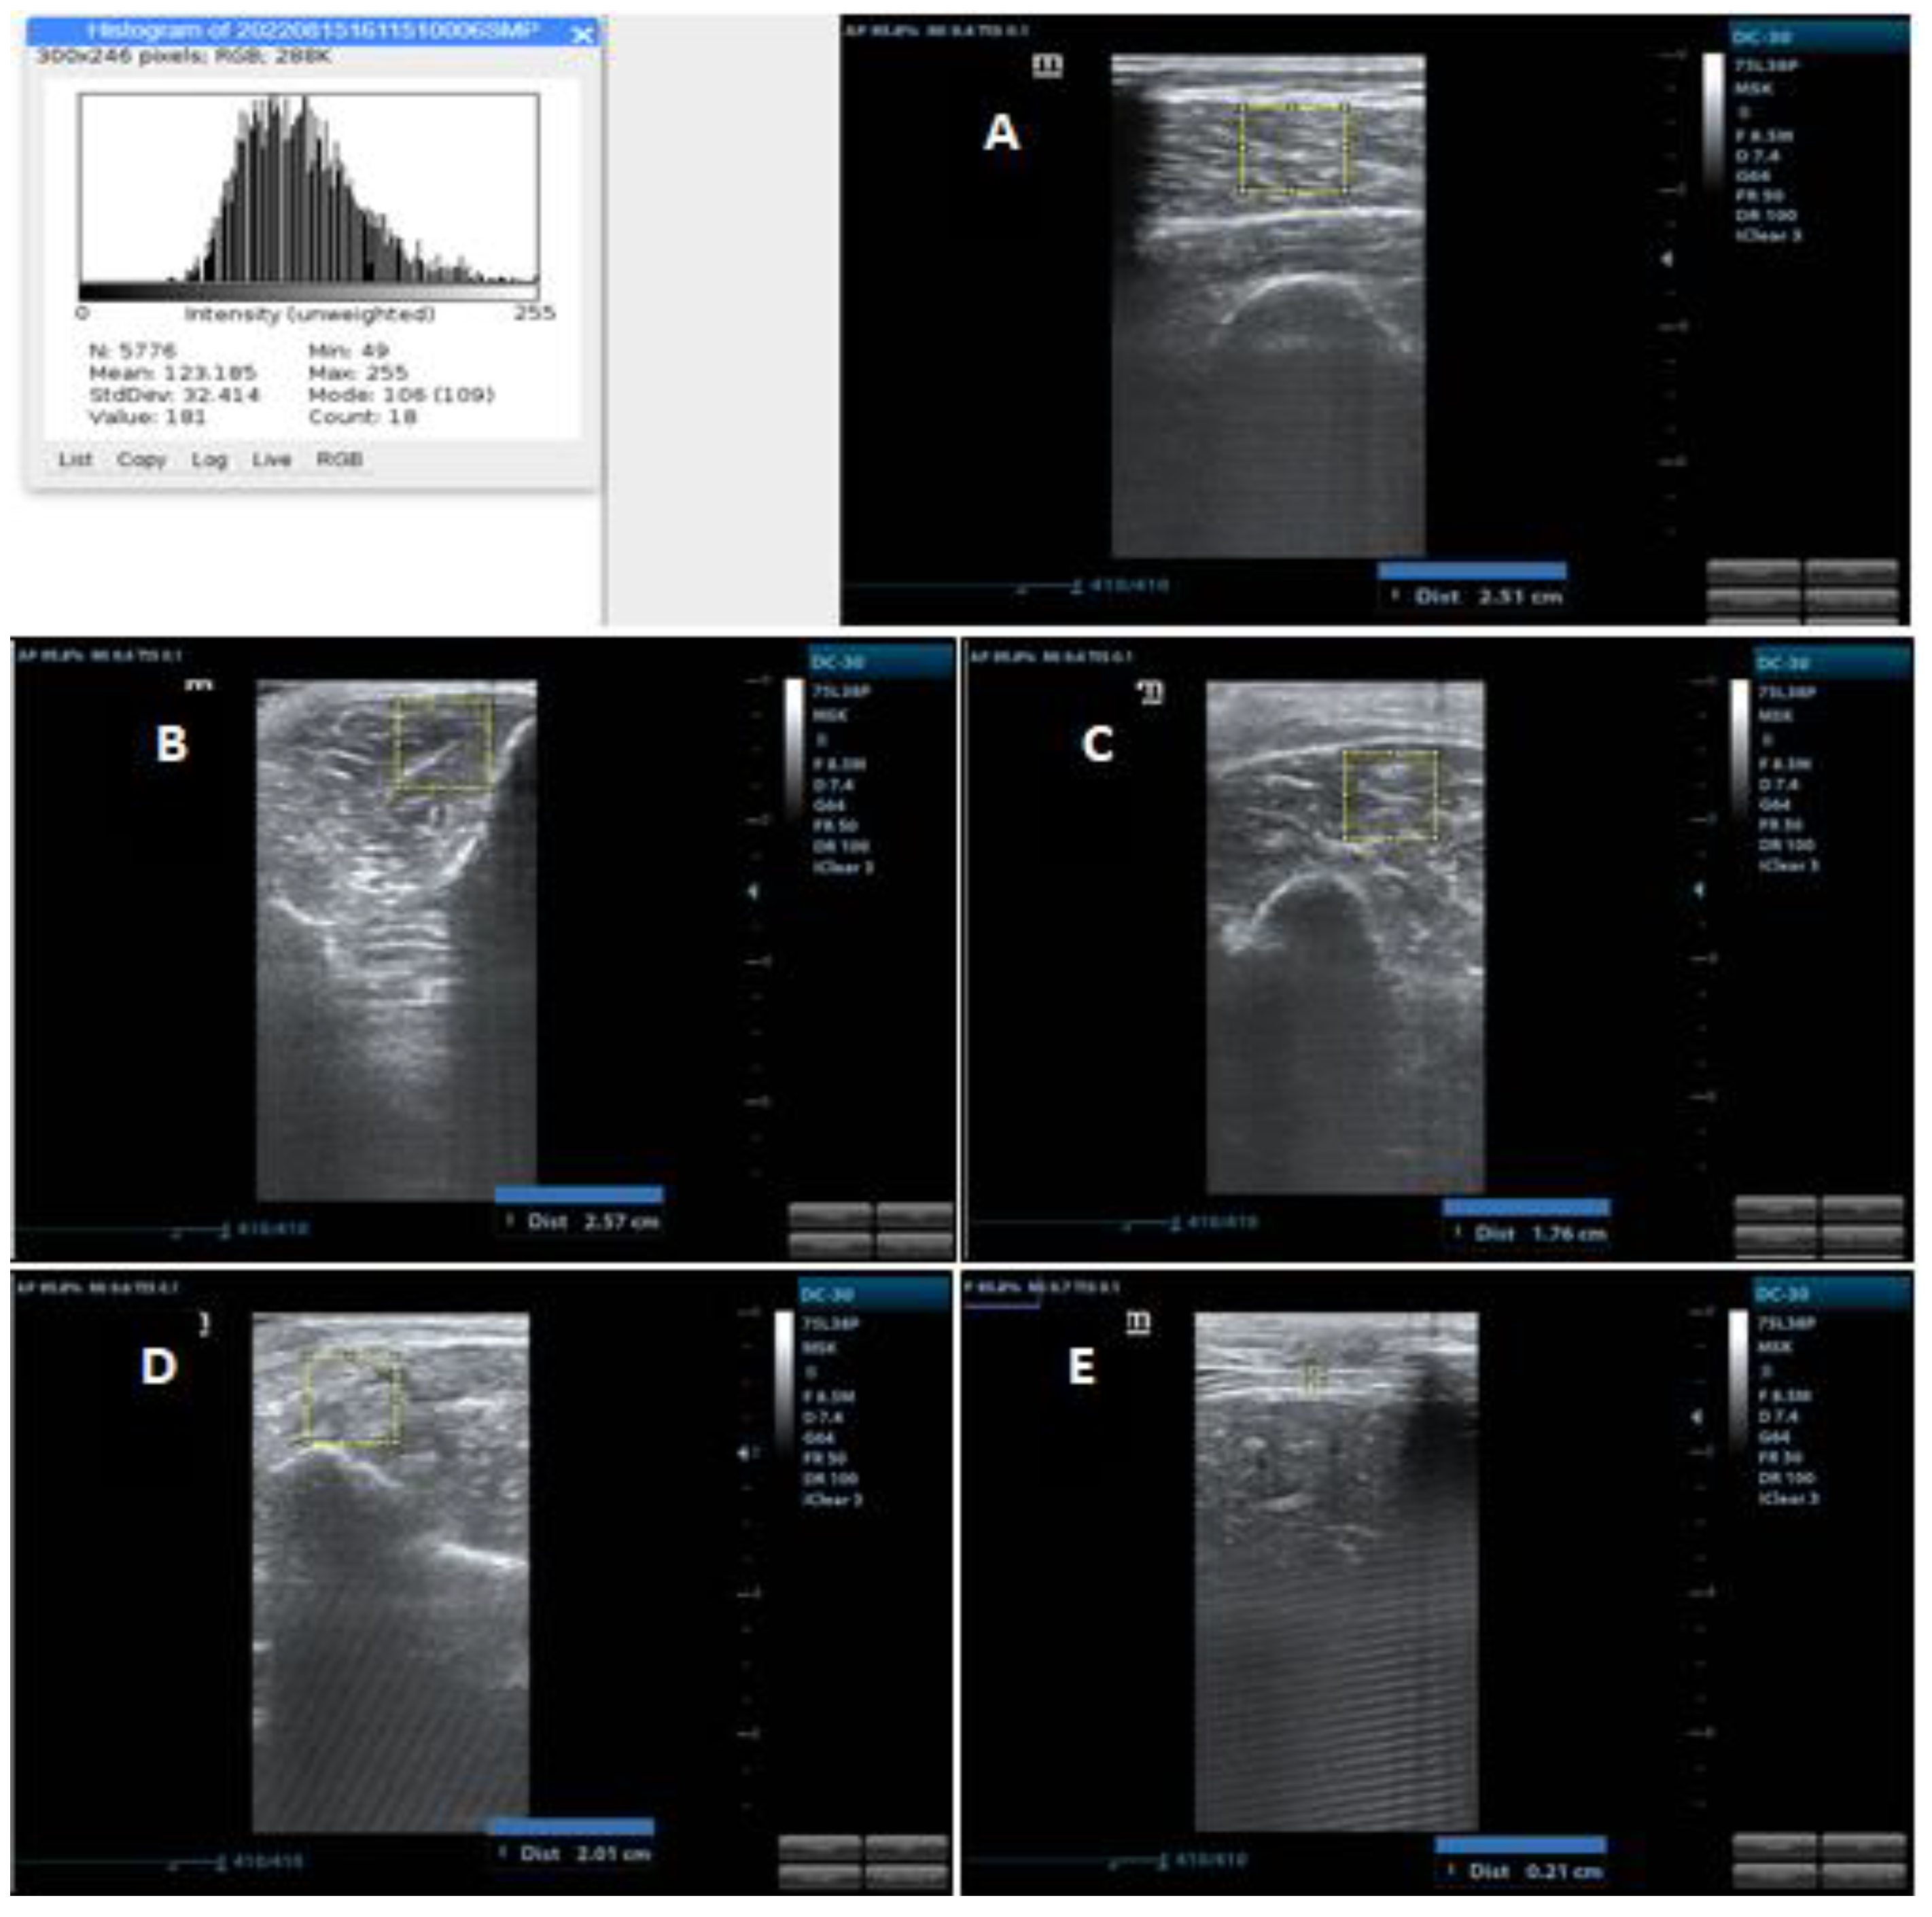

2.4.1. Diaphragmatic Assessment

2.4.2. Peripheral Muscles Assessment

2.4.3. Muscle Thickness

2.4.4. Muscle Echogenicity